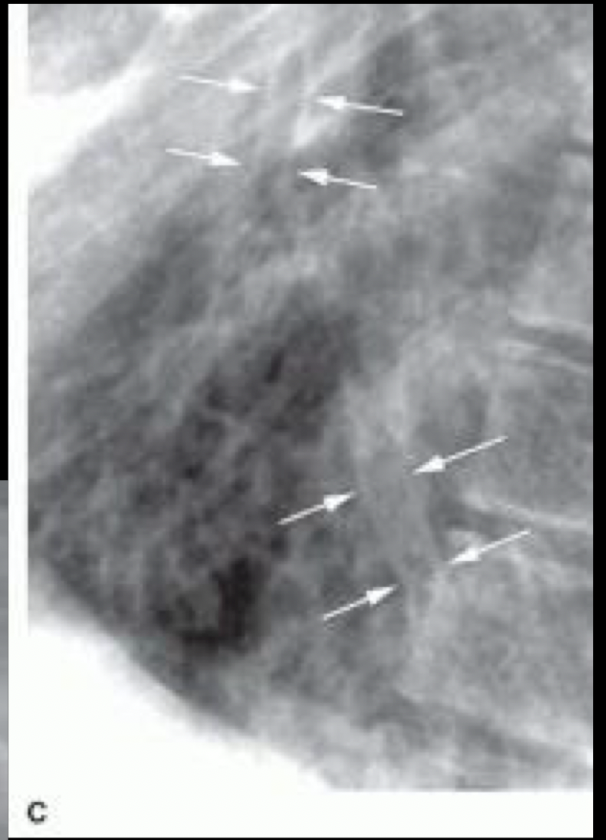

Esta lesión es característica de enfisema pulmonar, ¿cuál es y por qué piensas que es esta?

A

Bullas, paredes delgadas e irregulares